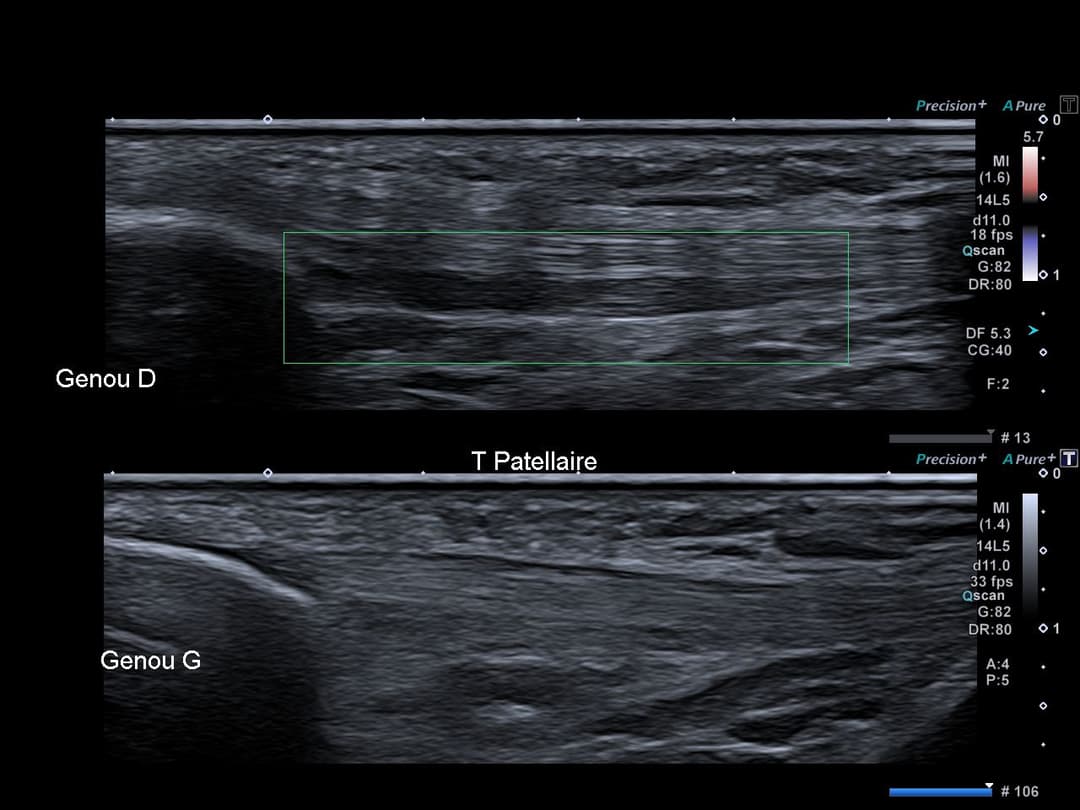

Échographie

Tendon patellaire présentant une plage de remaniement structurel modérément hypoéchogène, sans perte du caractère fibrillaire intéressant la face profonde du tendon sur 3 cm de grand axe, sans activité en Doppler.